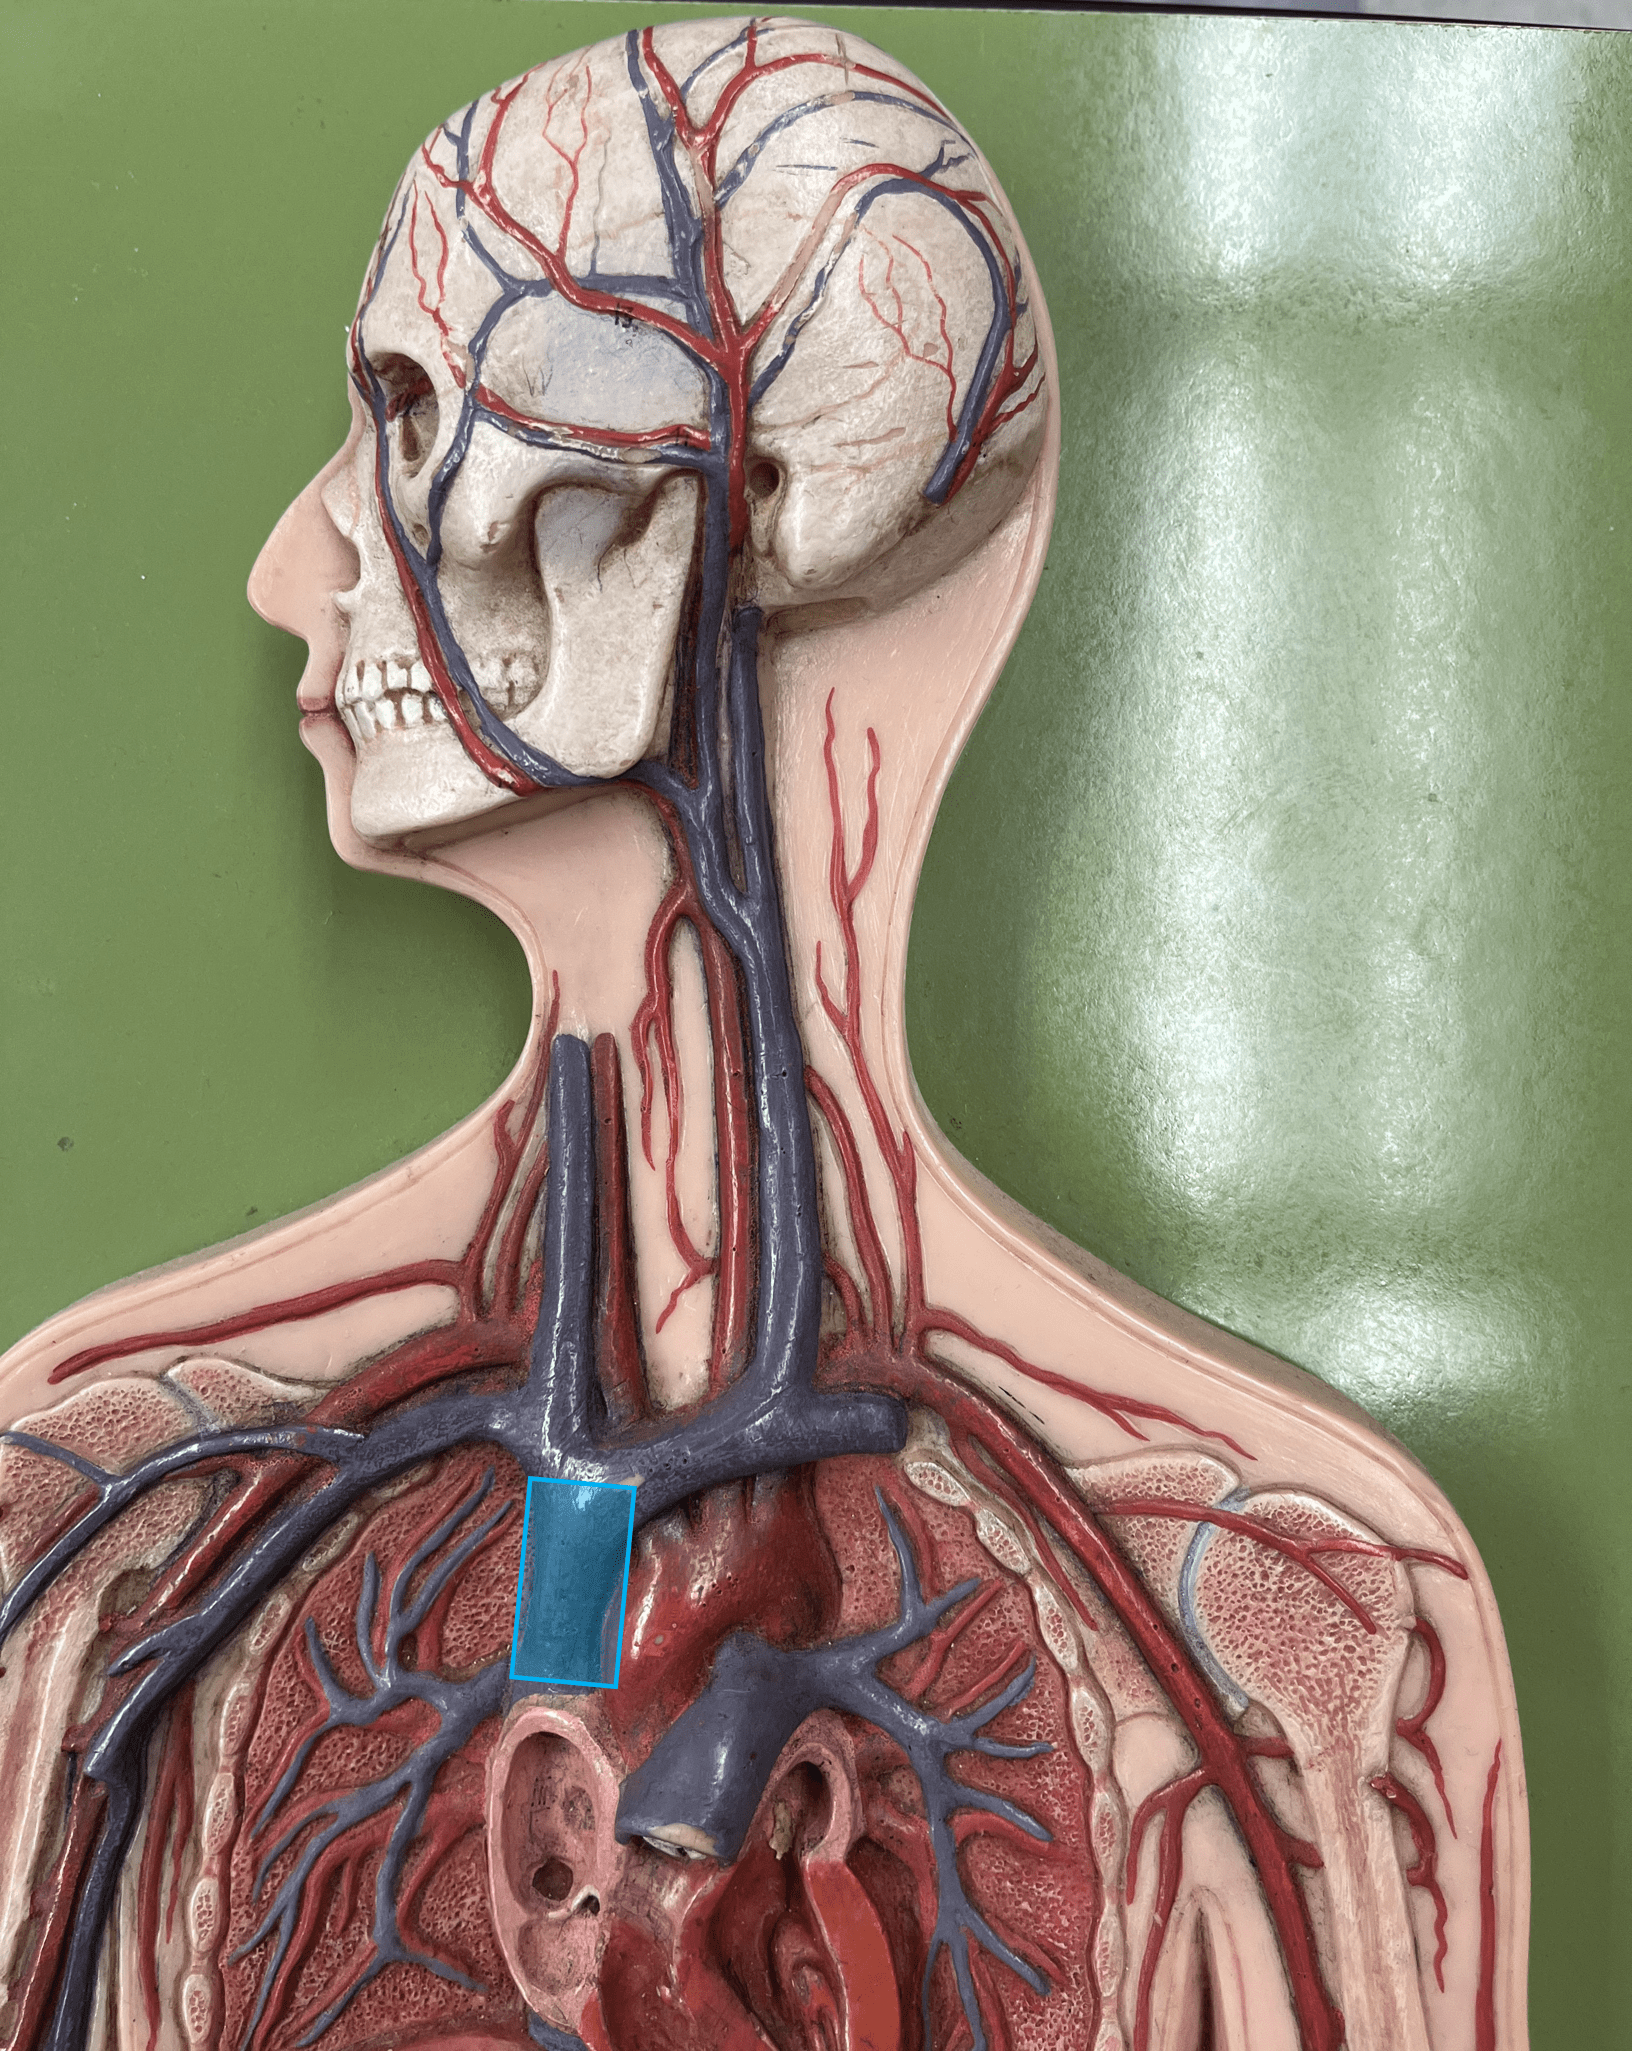

superior vena cava

• A vein of the thorax.

• Drains the azygos and brachiocephalic veins.

• Empties into the right atrium.

• Drains the azygos and brachiocephalic veins.

• Empties into the right atrium.

brachiocephalic vein

• A vein of the thorax.

• Drains the subclavian, external jugular, vertebral, internal jugular, and left intercostal (1-3) veins.

• Empties into the superior vena cava.

• Drains the subclavian, external jugular, vertebral, internal jugular, and left intercostal (1-3) veins.

• Empties into the superior vena cava.